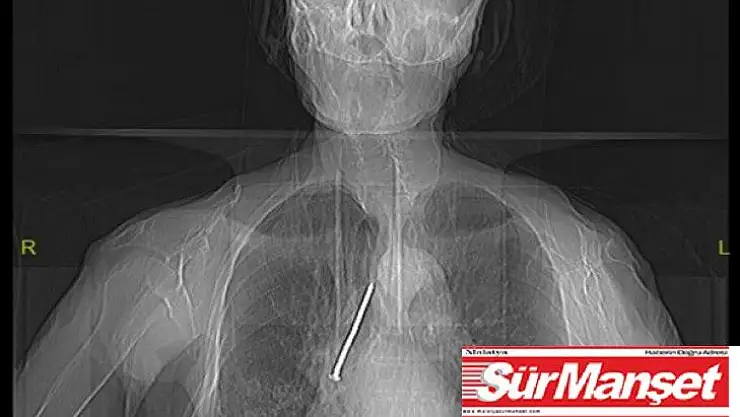

Elazığ'da, hastaneye başvuran 91 yaşındaki Keko Ateş'in nefes borusuna kaçan 10 santimetrelik inşaat çivisi, yapılan operasyonla başarılı bir şekilde çıkarıldı.

Hızlı bir şekilde müdahale edilmediği takdirde hayatı tehlikeye atabilen bir durumla karşı karşıya kaldıklarını belirten Dr. Kılıç, "Larenks kanseri nedeniyle 24 yıl önce boynundan nefes borusuna açılan açıklık aracılığıyla nefes alıp verebilen hasta, nefes borusundaki bu açıklığı temizlemek amacıyla kullandığı 10 santimlik çiviyi soluk borusuna kaçırmış. Bu nedenle gelişen öksürük ve nefes darlığı şikayeti ile önce başka bir sağlık merkezine başvurmuş, ardından Fethi Sekin Şehir Hastanemiz Göğüs Cerrahisi Kliniğine yönlendirilmiş. Biz de hastanede 91 yaşındaki hastamıza çektiğimiz tomografide soluk borusu içerisinde, sağ akciğer içerisine doğru kaçmış olan çiviyi tespit ettik” dedi.